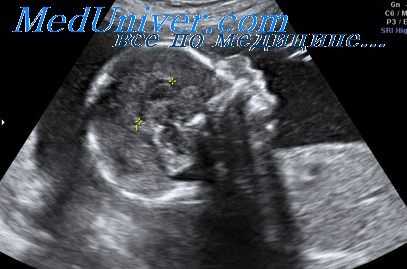

Тератома шеи плода

Тератомы представляют собой доброкачественные кистозные, кистозно-солидные или солидные опухоли. Они состоят из многих тканей, инородных по отношению к той ткани, в пределах которой они вырастают, и являются производными всех трех зародышевых листков. Опухоли такого рода, возникающие в переднем и заднем треугольниках шеи, исключая те случаи, когда в процесс вовлечены основание черепа и позвоночник шейного отдела, носят название цервикальных тератом.

Подразделение этих новообразований на тиреоидные и цервикальные тератомы в зависимости от наличия или отсутствия нормальной щитовидной железы или ее кровоснабжения не представляет клинического интереса и поэтому не будет нами рассмотрено. Почти во всех случаях цервикальных тератом, расположенных на передней поверхности шеи, наблюдается тесная связь ткани опухоли со щитовидной железой.

Антенатально возникшие новообразования составляют только 2,6% от всех опухолей, выявляемых у детей. Среди тех, которые формируются во внутриутробном периоде, 35% составляют тератомы, 80% из которых локализуются в пояснично-крестцовом отделе, вызывая анатомические и функциональные урогенитальные и аноректальные нарушения. Цервикальные тератомы встречаются значительно реже.

Несмотря на то что большинство таких опухолей оказываются доброкачественными, исход для плода и новорожденного нередко неблагоприятен. Частота таких осложнений, как многоводие, преждевременные роды и перинатальная смертность, при этом составляет 25%, 17% и 43% соответственно.

При очень больших по размеру цервикальных тератомах (когда один из ее размеров превышает 80 мм) частота преждевременных родов, дискоординации родовой деятельности или родоразрешения при помощи кесарева сечения увеличивается более чем на 50%. Нарушение процесса глотания у плода сопровождается развитием многоводия.

Смещение гортани и трахеи приводит к компрессии пищевода и подавлению глотательных движений плода. Однако тератомы меньшего размера (50 мм), при которых компрессионные осложнения под влиянием объема опухоли представляются сомнительным, также часто сочетаются с многоводием.

Возможно, это также связано с отрицательным влиянием на процесс глотания сдавления подъязычного нерва растущей опухолью.